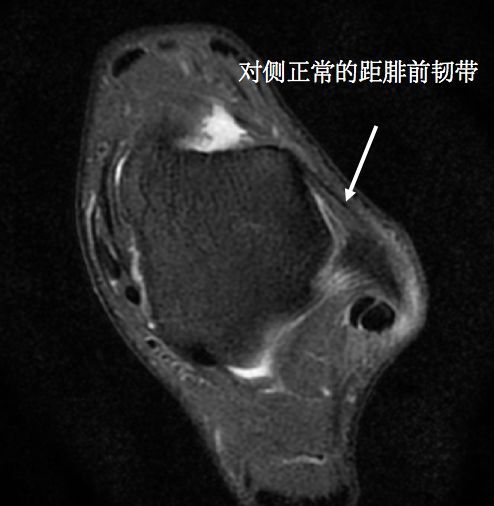

踝关节反复扭伤患者在追问病史时多可发现患者在首次踝关节受伤时会伴随有踝关节明显肿胀,这种表现往往代表维持关节稳定的外侧副韧带尤其是距腓前韧带损伤。但是很多人却认为不需特殊治疗,等待肿胀消退后就会自行好转,在首次受伤后没有得到及时的正规治疗,或者治疗方法不当,导致保护踝关节稳定的韧带没有愈合,从而使踝关节稳定性下降,导致踝关节更容易扭伤。很多人表现为走不平的路或者女性穿高跟鞋时候踝关节有明显的肿痛或者不稳定感觉,也有一部分人走路时会出现打软腿症状。

(踝关节距腓前韧带损伤)

(正常的距腓前韧带)